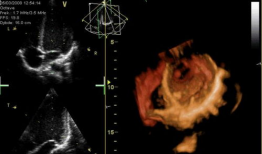

心脏跳动的视频,揭秘心脏跳动的奥秘

你知道吗?最近在网上流传着一个特别神奇的视频,它记录了心脏跳动的瞬间。这可不是普通的视频,它让我们仿佛能感受到心跳的力量,那种感...